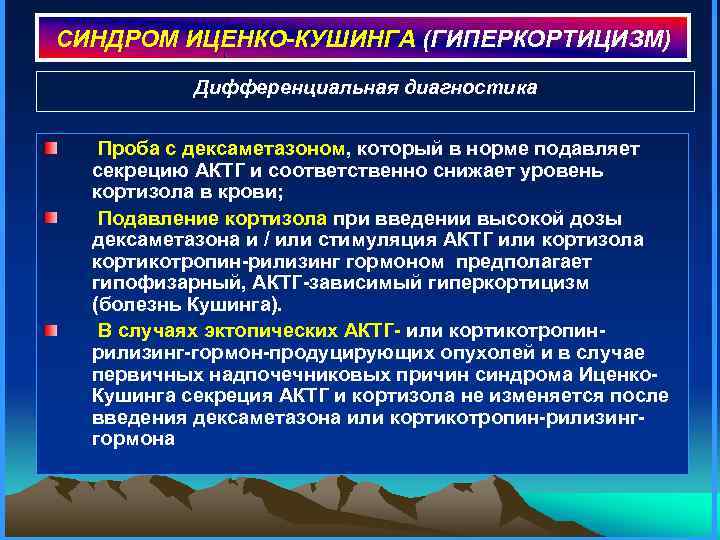

СИНДРОМ ИЦЕНКО-КУШИНГА (ГИПЕРКОРТИЦИЗМ) Дифференциальная диагностика Проба с дексаметазоном, который в норме подавляет секрецию АКТГ и соответственно снижает уровень кортизола в крови; Подавление кортизола при введении высокой дозы дексаметазона и / или стимуляция АКТГ или кортизола кортикотропин-рилизинг гормоном предполагает гипофизарный, АКТГ-зависимый гиперкортицизм (болезнь Кушинга). В случаях эктопических АКТГ- или кортикотропинрилизинг-гормон-продуцирующих опухолей и в случае первичных надпочечниковых причин синдрома Иценко. Кушинга секреция АКТГ и кортизола не изменяется после введения дексаметазона или кортикотропин-рилизинггормона

СИНДРОМ ИЦЕНКО-КУШИНГА (ГИПЕРКОРТИЦИЗМ) Дифференциальная диагностика Проба с дексаметазоном, который в норме подавляет секрецию АКТГ и соответственно снижает уровень кортизола в крови; Подавление кортизола при введении высокой дозы дексаметазона и / или стимуляция АКТГ или кортизола кортикотропин-рилизинг гормоном предполагает гипофизарный, АКТГ-зависимый гиперкортицизм (болезнь Кушинга). В случаях эктопических АКТГ- или кортикотропинрилизинг-гормон-продуцирующих опухолей и в случае первичных надпочечниковых причин синдрома Иценко. Кушинга секреция АКТГ и кортизола не изменяется после введения дексаметазона или кортикотропин-рилизинггормона